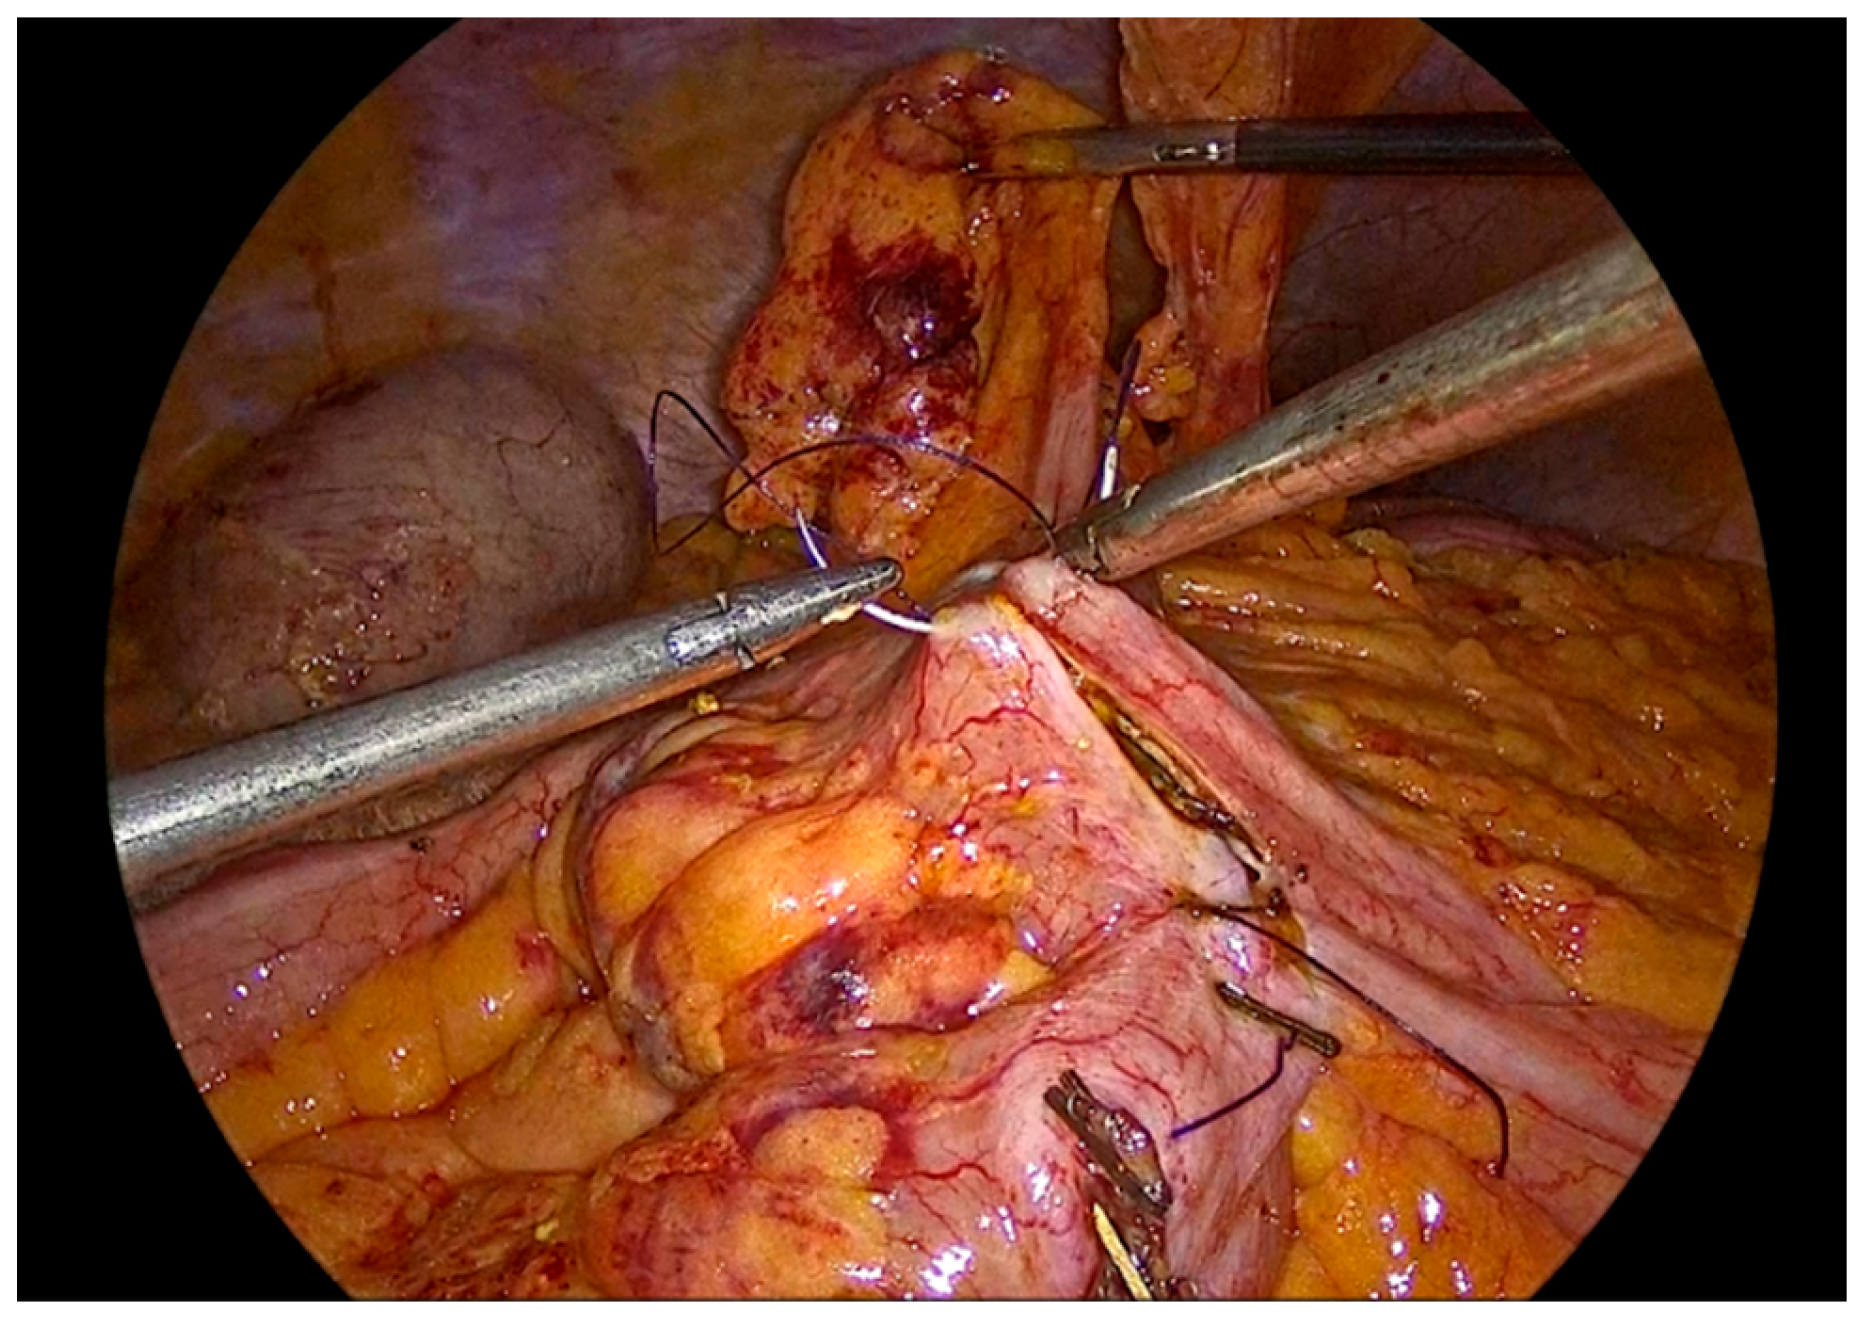

The inner layer of the anastomosis is constructed using a continuous full-thickness absorbable 3-0 Vicryl Plus suture, initiated proximally to the surgeon. Suturing proceeds from the proximal aspect toward the antimesenteric border, incorporating all the layers of the bowel lumen, with bites placed at intervals of 0,5 to 1 cm. Upon reaching the distal end of the enterotomy, the suture is continued along the opposite side, and the anterior layer of the anastomosis is completed after reaching back the proximal initial part of the anastomosis and tying the suture and to the initial knot.

Figure 8. First suture of the anastomosis, using an absorbable 3-0 Vicryl Plus suture.

Preprints 195043 g008

Figure 9. The inner layer of the anastomosis.

Preprints 195043 g009

Figure 10. Completion of the inner full-thickness layer of the anastomosis and transition to construction of the anterior layer.

Preprints 195043 g010

Figure 11. Anterior outer layer of the anastomosis.

Preprints 195043 g011